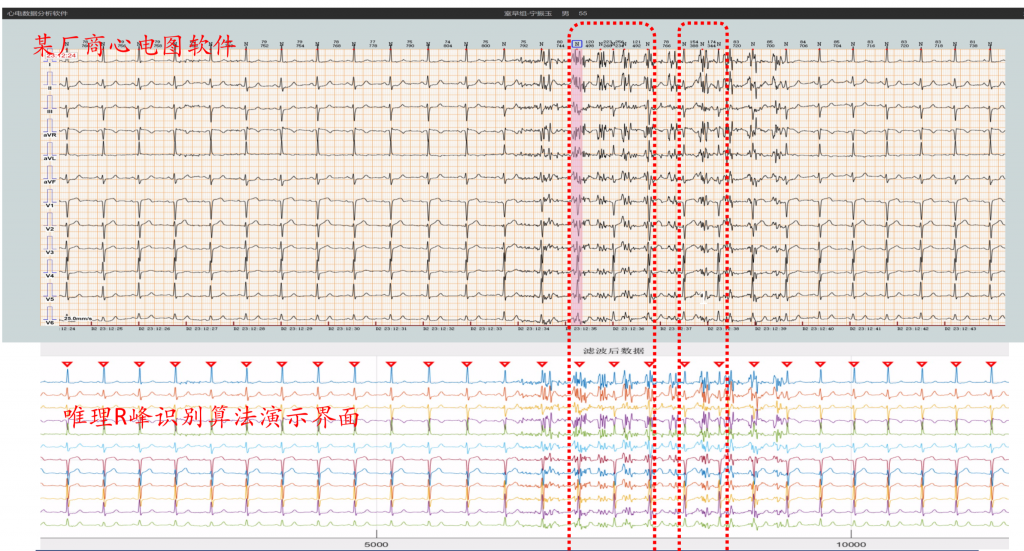

R峰识别准确率展示

R峰识别准确率展示